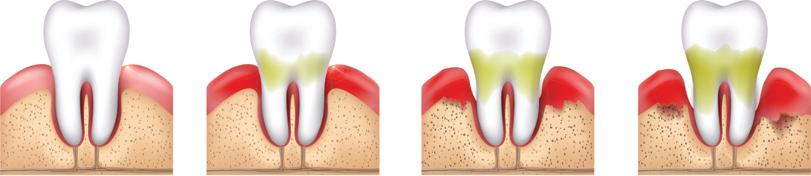

Bakterien können auch dazu führen, dass sich das Zahnfleisch entzündet. Es wird dunkler und beginnt zu bluten. Das Zahnfleisch bildet sich mit der Zeit zurück und auch der Kieferknochen wird angegriffen.

Abb. 7: Verlauf einer Zahnfleischentzündung